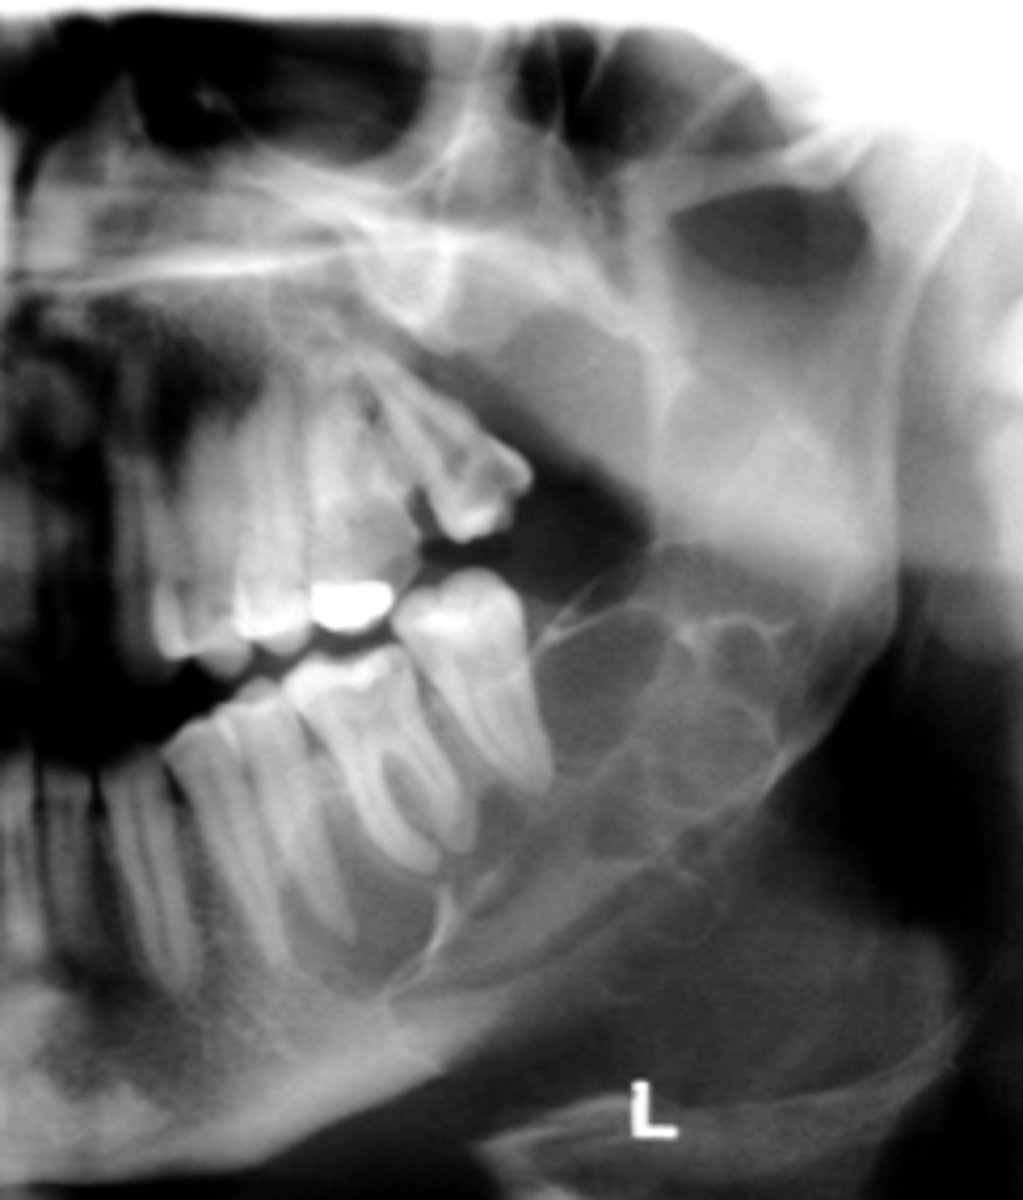

How would you describe the lesion?

- Periapical radiolucency associated with #30

- Has a band of sclerotic change extending from the apical radiolucency to the inferior alveolar canal and beyond

- Furcation involvement

(Furcation involvement as well as a band of sclerotic change extending from the apical radiolucency to the inferior alveolar canal and beyond)

What category would you put this lesion into?

Inflammation

what could be a differential diagnosis for this lesion? (select all that apply)

A. PCOD

B. multiple myeloma

C. apical rarefying osteitis

D. chronic sclerosing osteomyelitis

Also note apical rarefying osteitis #14 ( remnant root fragments, no crown due to caries)